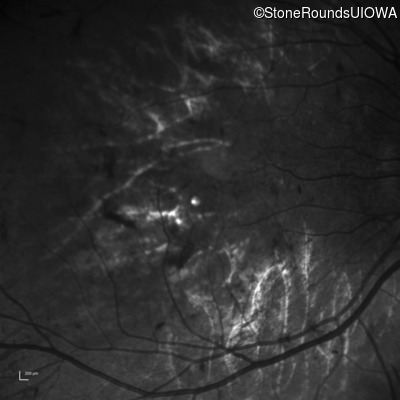

Infrared Fundus Photograph - Left - 5/160

Exemplar